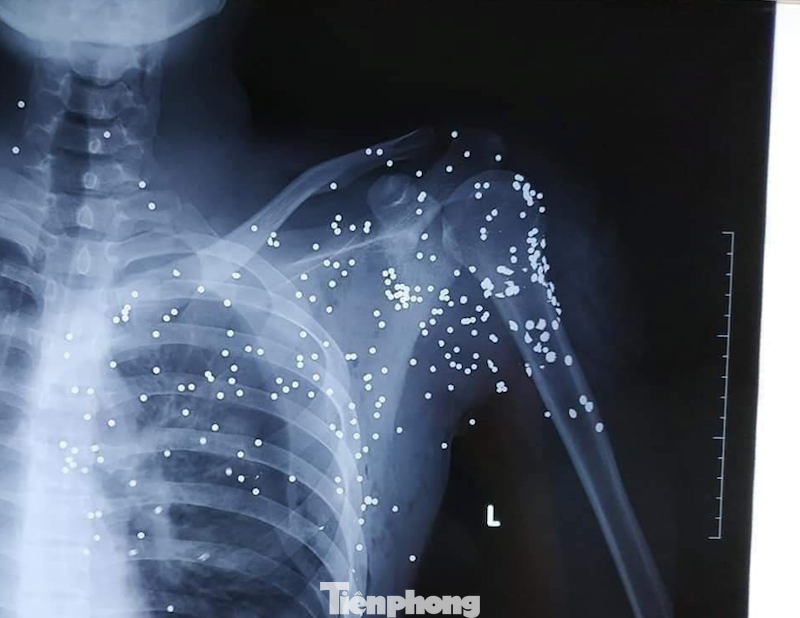

Phim chụp cho thấy nạn nhân bị mảnh đạn hoa cải găm kín phần ngực - Ảnh: HL

Thấy Đại mở của xe, cầm súng trên tay, đám thanh niên xô nhau chạy. Riêng Bùi Huy Hoàng (19 tuổi, trú tại huyện Kiến Xương, tỉnh Thái Bình) do đứng gần, lùi lại không kịp nên đã hứng trọn viên đạn "hoa cải" vào phần ngực.